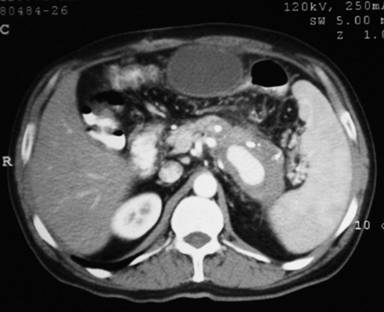

A hematological work-up, including hemoglobin and liver function tests, was normal. A contrast enhanced computed tomography scan (Figures 1 and 2) revealed features of chronic pancreatitis with multiple foci of calcifications in the pancreatic duct and parenchyma involving the body and tail. The pancreatic duct was not significantly dilated. There was a large pseudoaneurysm measuring 7x4 cm in size in the splenic artery. In addition, there was a pseudocyst measuring 6x4 cm in size in the omentum, separate from the pancreas.

Figure 1. CT scan showing calcification in the body and tail of the pancreas, pseudoaneurysm and pseudocyst separate from the pancreas. |